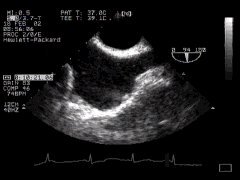

3. Two chamber view + LAA

4. The left atrial appendage is important. Here you can see that it often has coarse trabeculation, and in addition the junction of the left upper pulmonary vein and left atrium close to the LAA can give a mass-like effect.